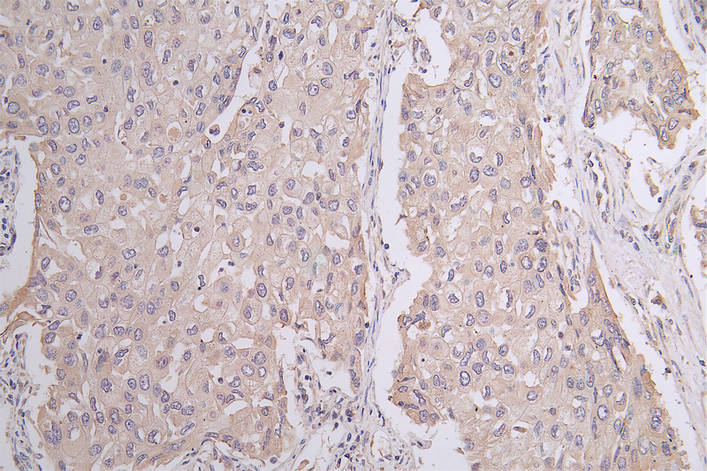

• IHC image of CSB-RA549607A0HU diluted at 1:50 and staining in paraffin-embedded human lung cancer performed on a Leica BondTM system. After dewaxing and hydration, antigen retrieval was mediated by high pressure in a citrate buffer (pH 6.0). Section was blocked with 10% normal goat serum 30min at RT. Then primary antibody (1% BSA) was incubated at 4°C overnight. The primary is detected by a Goat anti-rabbit polymer IgG labeled by HRP and visualized using 0.1:50% DAB.